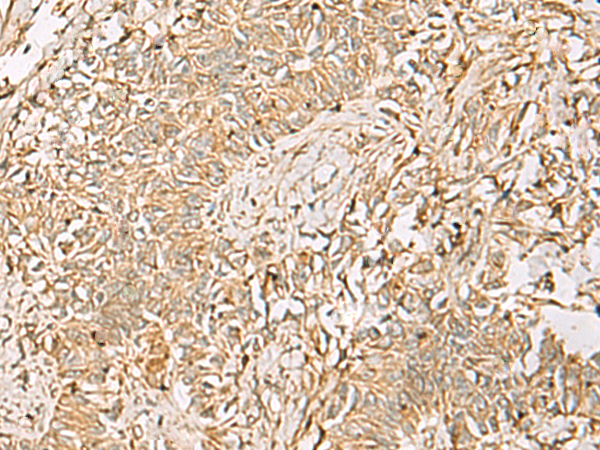

分类: 科研抗体货号: P02834别名: S11应用: WB,IHC反应种属: Human, Mouse, Rat